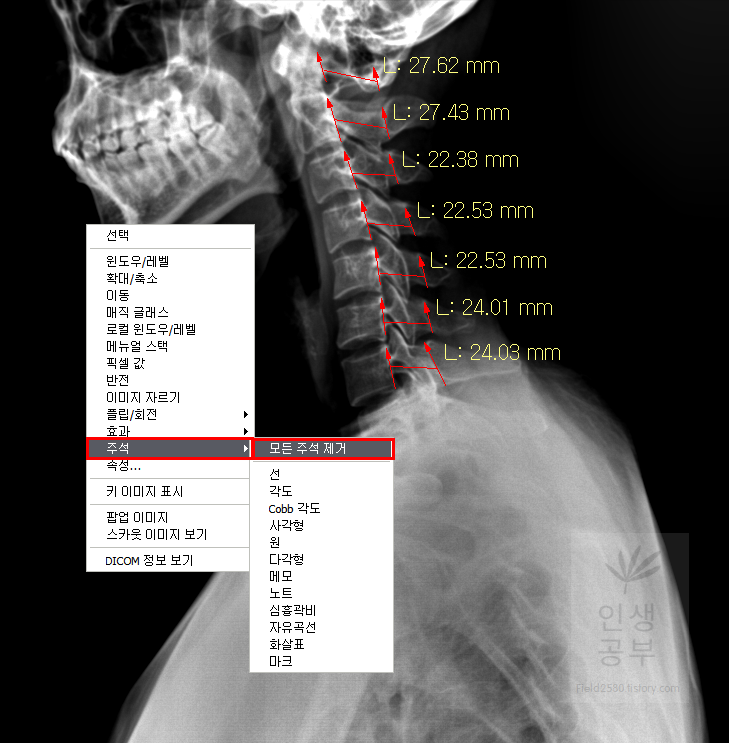

. Display Workstation 화면에 표시된 주석(선이나 각도 등) 없애는 방법

X-ray 화면에 선이나 각도 줄을 긋고, 각도를 측정한 후에 다시 화면을 깨끗하게 하고 싶을 때 사용하는 방법이 있습니다. 화면에 있는 전체 주석들을 삭제는 방법이 있고, 삭제하고자 원하는 주석만 선택적으로 삭제하는 방법이 있습니다. 삭제를 잘못했다 하더라도 위에 설명해드린 마지막으로 한 동작을 취소합니다 버튼과 이전에 취소한 동작을 다시 수행합니다 버튼을 이용해서 다시 나타나게 할 수 있으니 지워졌다고 너무 걱정하지 않으셔도 됩니다.

1) X-ray 화면에 있는 모든 주석(선, 각도, 메모, 노트, 화살표 등)을 모두 삭제하거나 주석 종류별 삭제하는 방법

X-ray 화면 상에서 마우스 오른쪽버튼을 눌러줍니다. 주석이라고 적힌 메뉴에 마우스를 가져다 놓습니다.

X-ray 화면 상에 있는 모든 주석들을 제거하고 싶으면 모든 주석 제거를 눌러주시면 됩니다. 만약 선이나 각도, 메모 등을 선택적으로 삭제하고 싶으면 아래에 있는 메뉴를 이용하면 됩니다. 예를 들어 선 삭제를 원한다면 X-ray화면 내에 있는 모든 선들이 삭제된다고 생각하시면 됩니다. 하나만 삭제하고 싶으실 때는 선택적 삭제하는 방법에 있는 방법을 이용하셔야 합니다.

모든 주석을 삭제하는 버튼을 누르면 아래와 같이 화면이 다시 깨끗해집니다. 다시 삭제한 주석을 돌리고 싶다면 마지막으로 한 동작을 취소합니다 버튼을 누르거나 단축키인 Ctrl+Z 버튼을 이용하시면 됩니다.